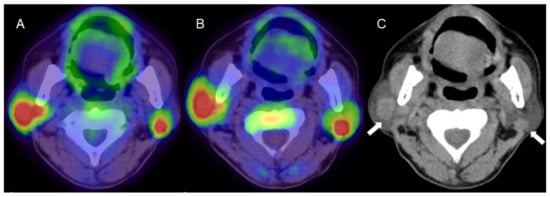

Figure 2.

A man in his 60s with pathologically proven Warthin’s tumor in the parotid glands bilaterally. (A) Fused FDG-PET/CT image (axial view), (B) fused 4DST PET/CT image (axial view), and (C) plain CT (axial view). Intense uptake of both FDG (SUVmax: 9.6) and 4DST PET/CT (SUVmax: 12.0) is seen in bilateral nodular lesions, which show high intensity on plain CT (arrows) consistent with the typical features of Warthin’s tumors. Aspiration biopsy revealed oncocytes and abundant lymph-node cells and epithelium with eosinophilic cytoplasm, and a diagnosis of Warthin’s tumor was made based on pathological findings.